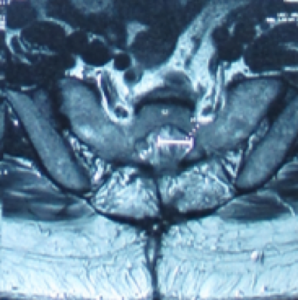

骶管襄腫一般生長於骶骨的第一節至第三節,內裹充滿了腦脊液, 襄腫可逐漸增大導致馬尾神經線被壓迫, 引起神經根發炎或產生脊髓病變及令骨性結構也被侵入破壞.。磁力共振檢查可清楚分辨骶管襄腫的位置,大小及與硬脊膜和神經根的關係。

一般細小的骶管襄腫多數不會引起任何問題.但如病人的徵狀引起神經缺損而嚴重地影響日常生活, 手術介入可能是最好的選擇。 手術經腦神經外科醫生處理,以微創手術,將襄腫抽吸腦脊液,再封堵阻止脊液進入,然後拿取病人身體的脂肪或肌肉來填塞襄腫空間。( 圖ー , 圖ニ)